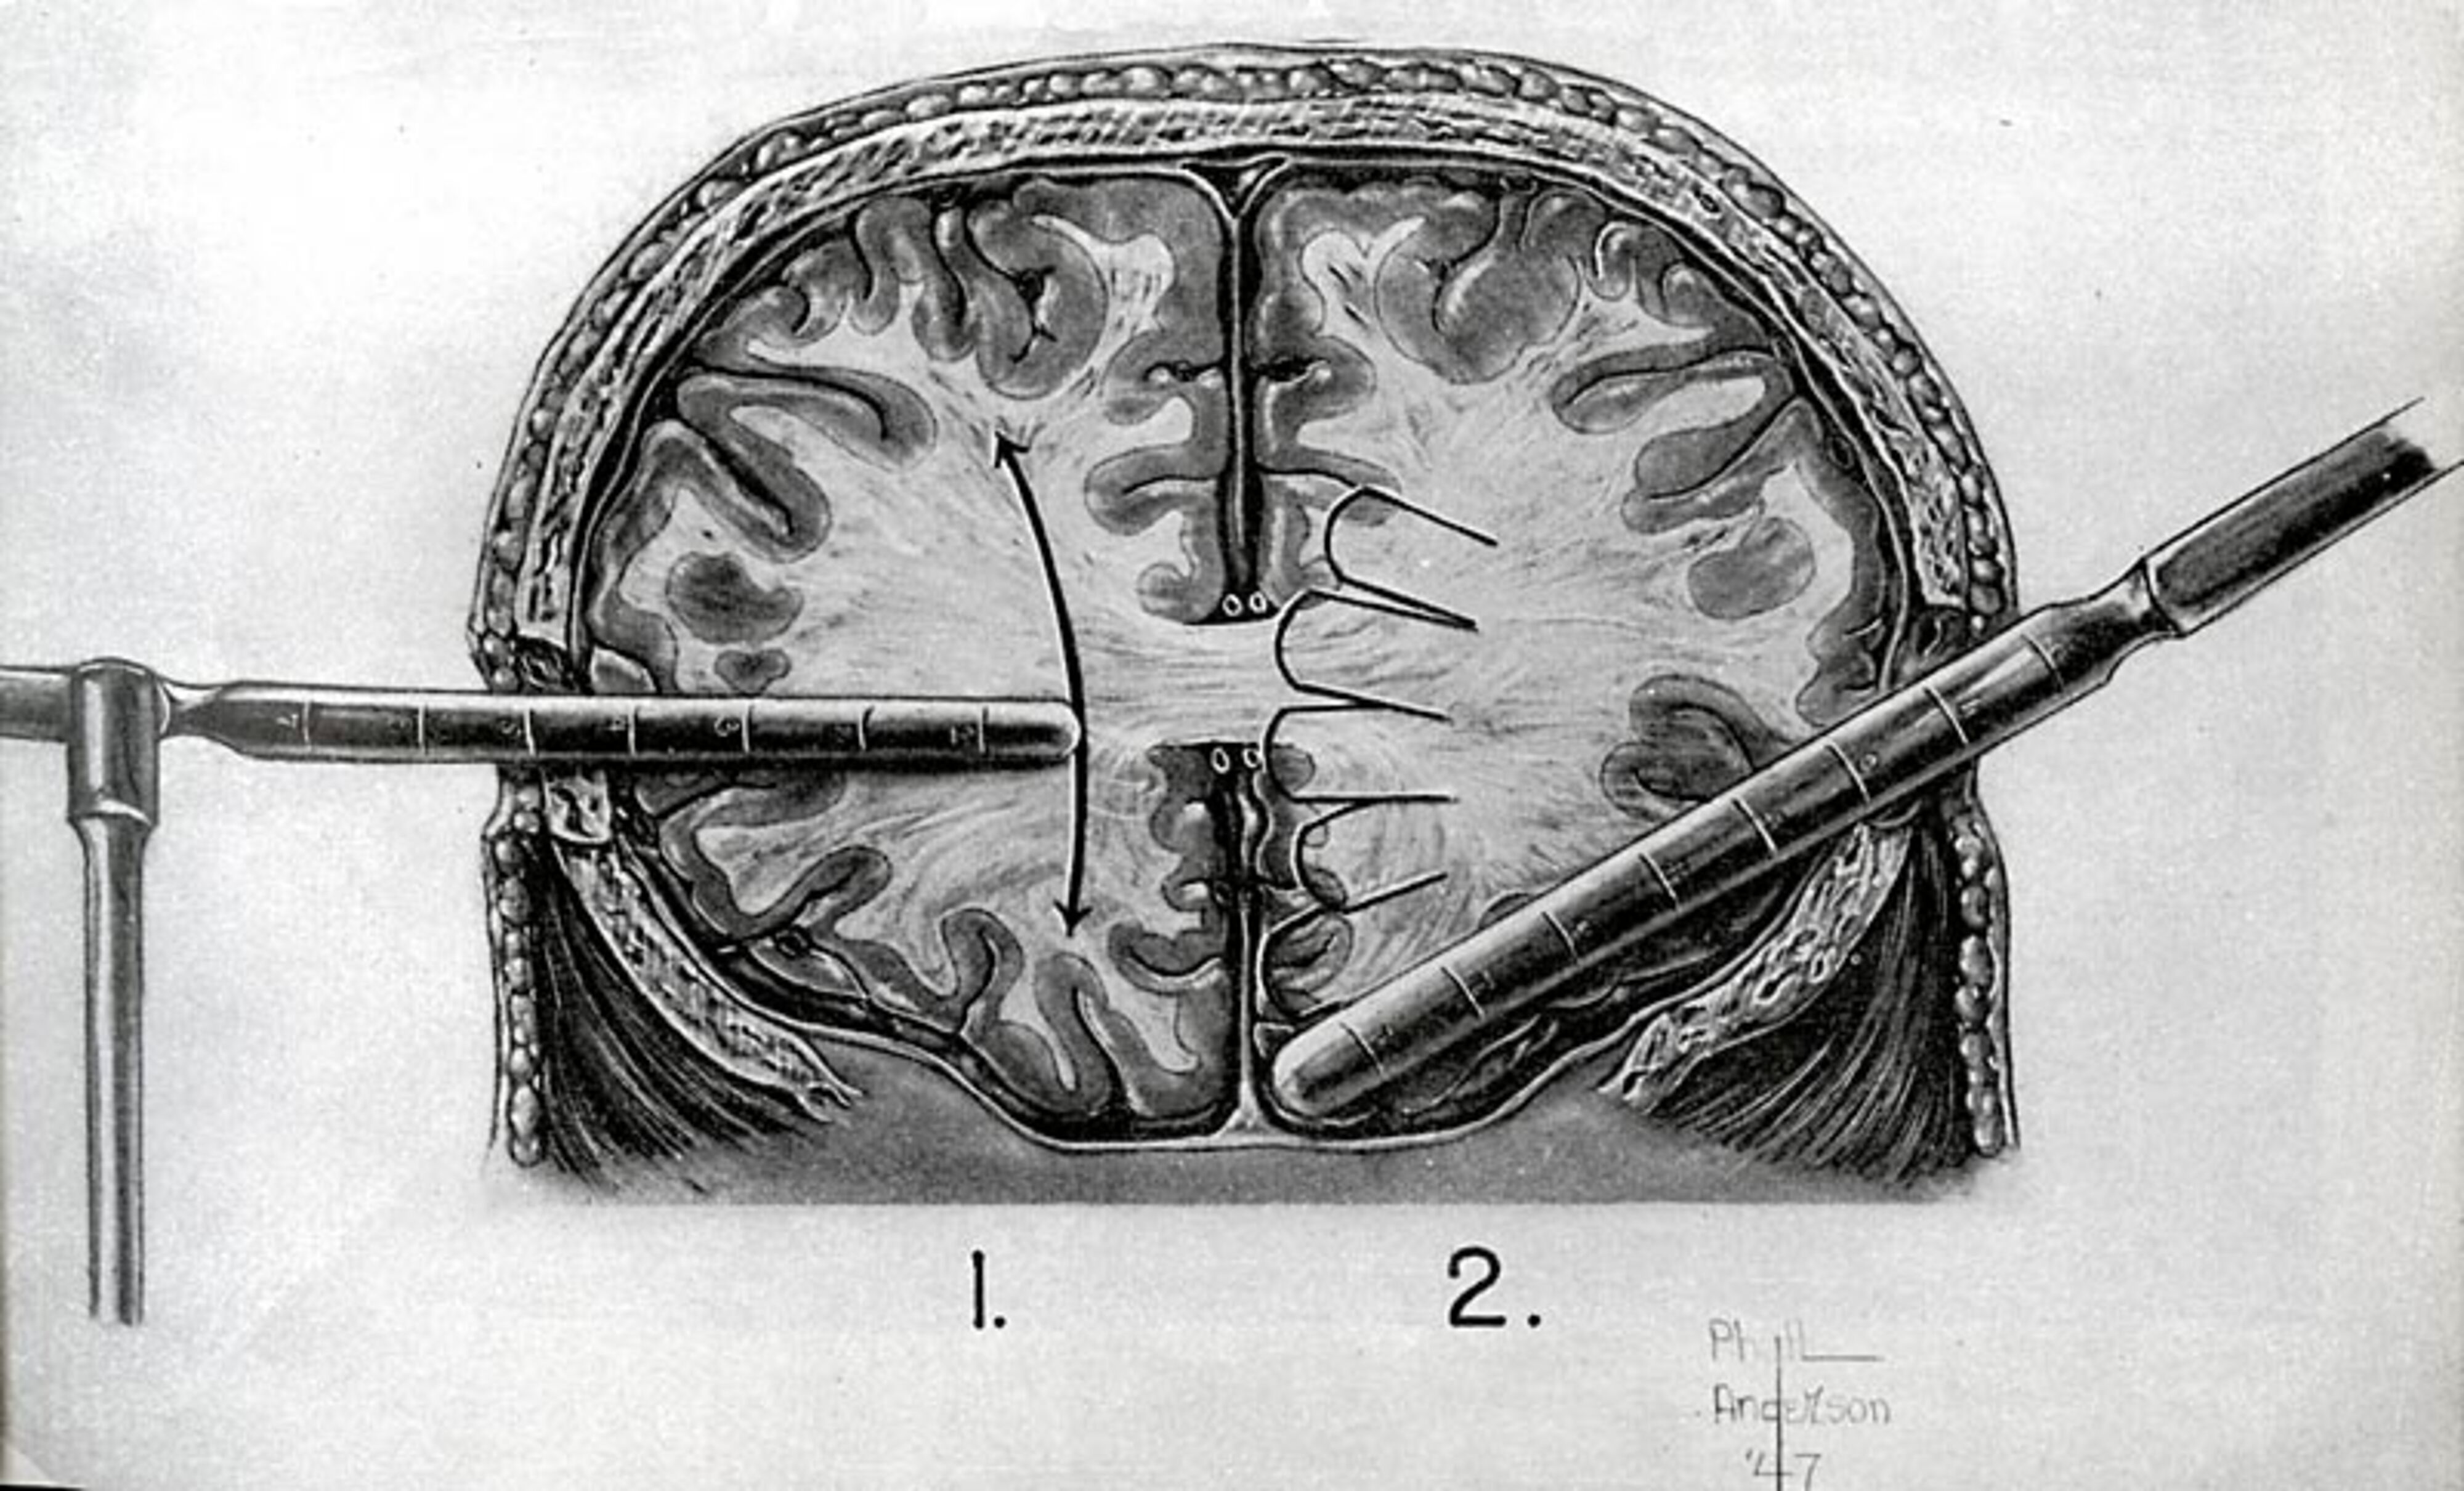

Lobotomi

En af de behandlingsformer, som var ret udbredt i Danmark fra 1939 til starten af 1950erne, var lobotomien, også kaldt "Det hvide snit". Metoden gik ud på, at man overskar nervebaner fra pandelappen til nogle dybere liggende områder i hjernen, som er centrum for følelseslivet. Man mente, at denne operation kunne dæmpe følelsen af angst og uro, som var et problem for mange patienter.

På sindssygehospitalerne var mange patienter, der f.eks. led af skizofreni, indlagt på urolige afdelinger, hvor man ikke kunne gøre så meget for at hjælpe dem. På nogle patienter virkede den beroligende medicin ikke, og de lå fastspændt i deres senge i lange perioder. Man mente at lobotomien kunne hjælpe disse patienter, da operationen kunne gøre dem mere rolige og evt. betyde, at de kunne sendes hjem til familien.

Operationen kunne kun udføres efter en læges indstilling og hvis familien gav deres samtykke. Operationen var hurtig, men ikke ufarlig. Op imod 6% af patienterne døde som følge af indgrebet. Men der var ingen garanti for succes, og desuden opstod der visse bivirkninger. Nogle patienter blev nemlig ikke bare rolige, men helt apatiske, og flere ændrede tydeligt personlighed. Når operationen først var gennemført, var den permanent, dvs. man kunne ikke genskabe nerveforbindelserne i hjernen. Patienterne var resten af deres liv påvirket af denne operation.

I løbet af 1950erne ophørte man næsten helt med at udføre indgrebet. Der var efterhånden kommet flere forskellige former for medicin, der kunne anvendes til at berolige patienterne. Desuden rejste der sig en voldsom kritik af behandlingen, der havde fået store konsekvenser for nogle af de personer, der blev opereret. Herefter var det kun i særlige tilfælde, at operationen blev udført. Der blev udført lobotomi på 4500 personer fra 1939 til 1983, hvor operationen blev indstillet herhjemme.